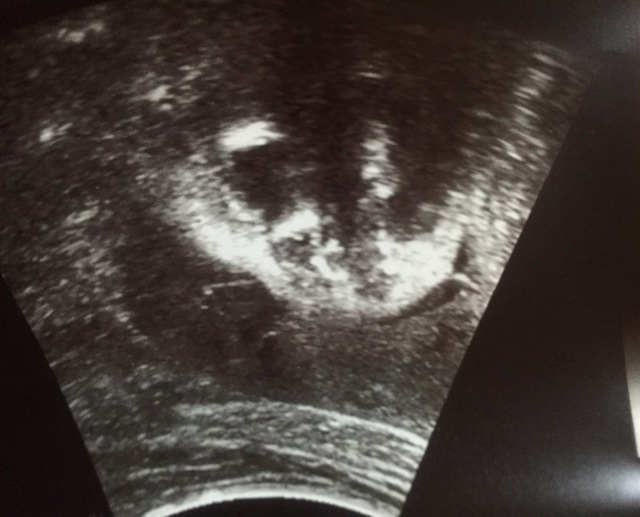

32週6日(32w6d・男の子)|ひーちゃんad さん(26歳)

エコー写真撮影時のエピソード:

可愛い可愛いおちんちんがうつりました!!先生から聞いた性別が男の子、女の子、男の子と何度か性別が変わりました。どっちなんだ!とそわそわしてましたが、これは完全に男の子と判明!女の子でも男の子でも嬉しいですが、最初は男の子がいいなーと思ってたので嬉しかったです。これで安心して男物の洋服などが揃えられます!!早く会えるのを楽しみにしてます^ ^